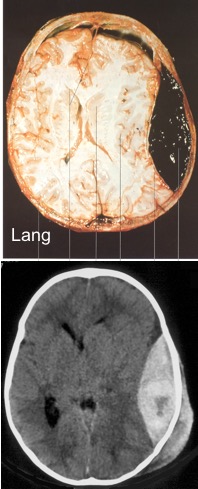

l’HED constitué est de consistence hétérogène, en partie caillot solide, en partie

surnageant liquide (sérum) ; le scanner montre donc une image de densités différentes. en raison des caillots denses (ci-contre) ; l’espoir d’un « trou de trépan salvateur » est fallacieux.